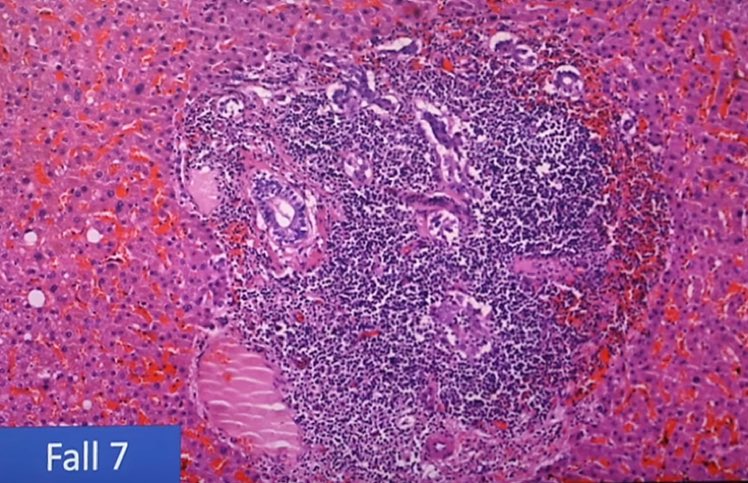

التهاب عضلة القلب اللمفاوي ، التهاب غشاء القلب ، التهاب التامور ، "غلبة الخلايا الليمفاوية" :

⁃نموذجي للعدوى الفيروسية

⁃يصعب التعرف عليها بالميكروسكوب ،

⁃غالبًا ما يُساء تفسيرها من الناحية النسيجية على أنها معدية (الخلايا الحبيبية!). 6️⃣

- ظواهر المناعة الذاتية ("الهجوم الذاتي")

-انخفاض القدرة المناعية ،

-التأثير على نمو السرطان.

-تلف الأوعية الدموية "التهاب البطانة" ، التهاب الأوعية الدموية ،